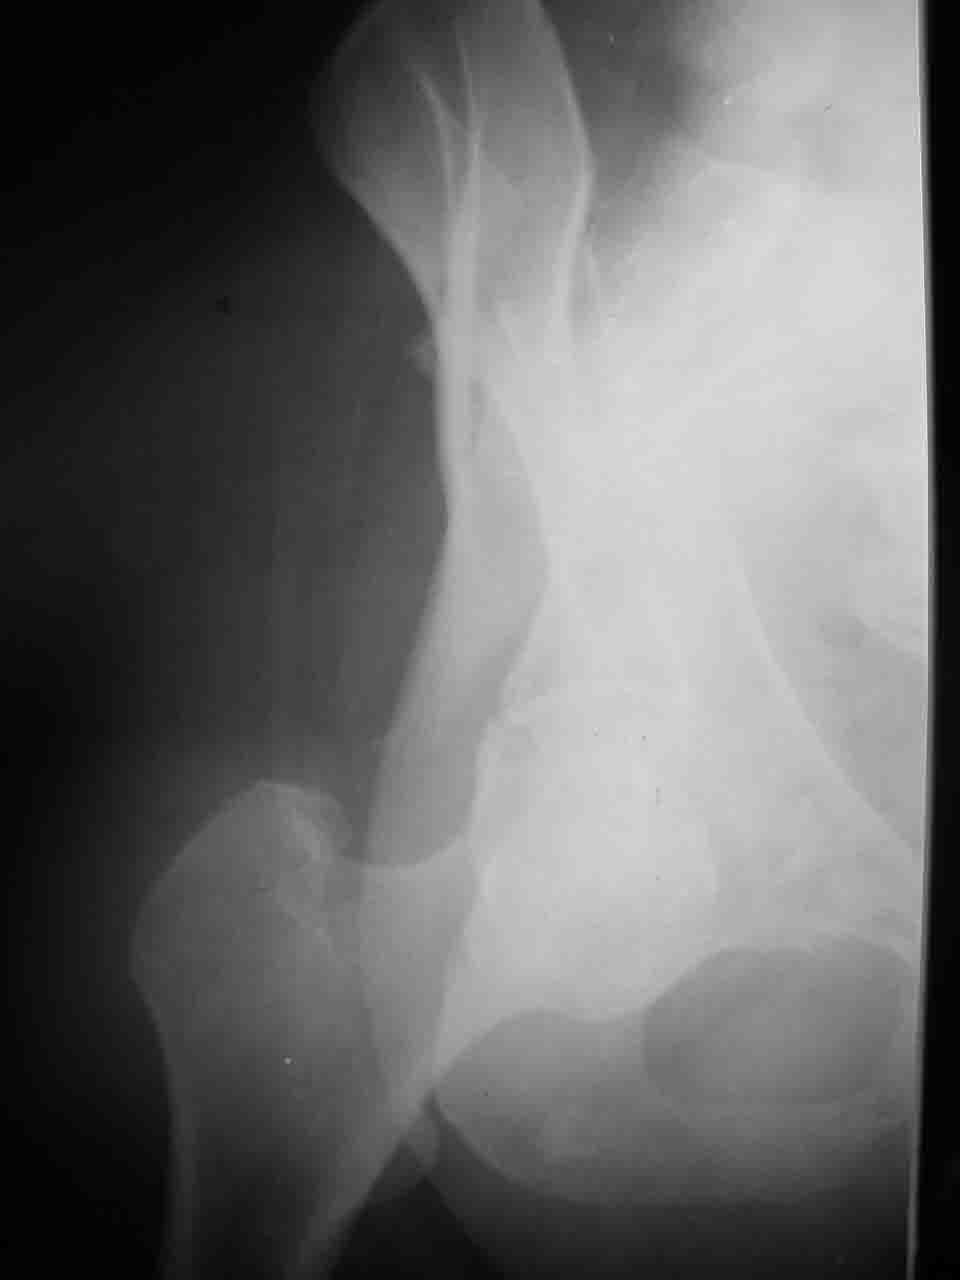

Re: Перелом вертлужной впадины

Смирнов Алексей 09 Ноябрь 2004, 01:17

Снимки и схема